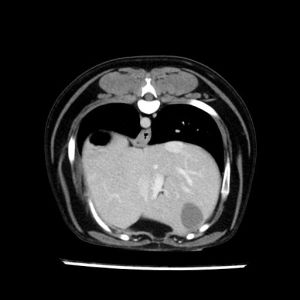

La lesione focale epatica , la ceus,la Tac e il chirurgo .